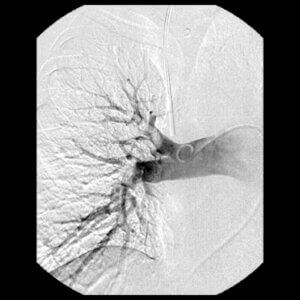

This image is from a pulmonary angiogram of the right lung, showing improvement of the PE after PMCDT.

With the resolution of a majority of the clot burden, we can document the relieved strain on the heart. At this point, we remove the catheters and with the help of the pulmonary critical care team, help you in your transition home as soon as possible, typically within a few days.